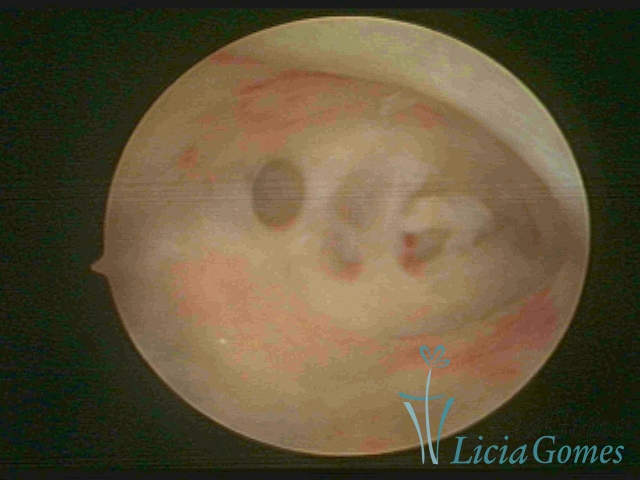

As Sinéquia uterinas são cicatrizes (aderências) entre as superfícies das paredes uterinas, que podem ocorrer após manipulação cirúrgica, ou curetagem uterina, ou após um processo inflamatório na cavidade uterina (endometrite), podendo levar a alterações menstruais, infertilidade, e complicações obstétricas, como abortamento, parto prematuro.